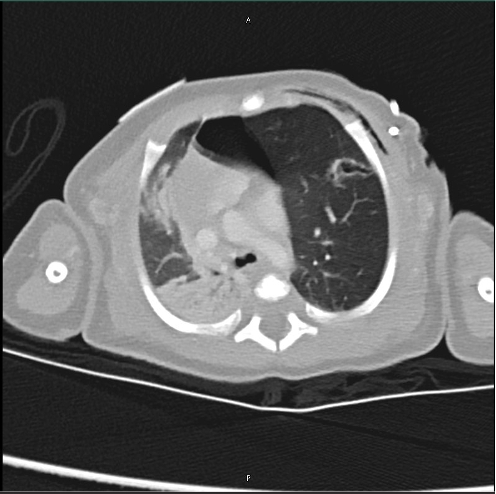

Due to an x-ray obtained while the patient was on the pediatrics floor, there were concerns for an underlying tension pneumothorax. The patient was transported to the PICU, where upon admission an urgent needle decompression was performed. However, upon performing the same, there was no change in the patient's vitals, nor was there a gush of air emitted from the needle that was placed. To further delineate the cause of the findings seen on the x-ray, a CT chest with IV contrast was performed (Figure 2). This image study confirmed the diagnosis of left upper lobe congenital emphysema. Her condition was managed with surgical resection of the left upper lobe emphysematous lobe. Her respiratory status improved after surgical resection with her breathing without any distress.

The diagnosis of CLE can be challenging as it may mimic other conditions such as tension pneumothorax or pulmonary interstitial emphysema.2 Chest X-rays and CT scans are the imaging modalities of choice to confirm the diagnosis. In this patient, the initial X-ray raised suspicion for CLE, which was later confirmed by a CT scan showing hyperinflation of the left upper lobe and atelectasis of the left lower lobe.